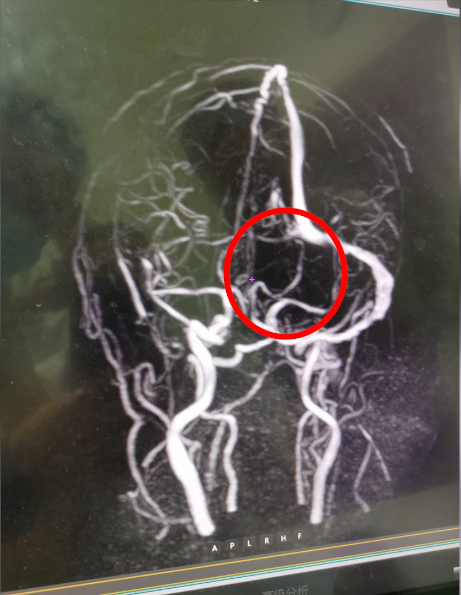

头晕呕吐在我们的生活中很常见,引起头晕呕吐的原因也很多。近日有一位脑囊虫病患收入我院,经过治疗症状刚有好转,又出现了头痛呕吐。我院医生高度重视,仔细检查排查后,确诊患者为左侧颅内静脉窦血栓形成。

头颅MRV检查发现血栓形成

该病在临床上并不多见,因此容易漏诊和误诊。患者经常被误诊为脑动脉性梗死、脑肿瘤、脑部感染等。CT核磁共振可看到间接征象,但直接征象主要依靠MR静脉成像(MRV)。